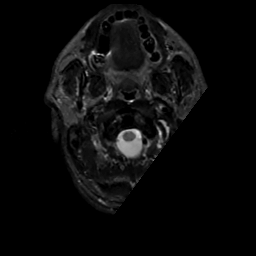

MR Study #6, March 17, 1991 -- Slice #0